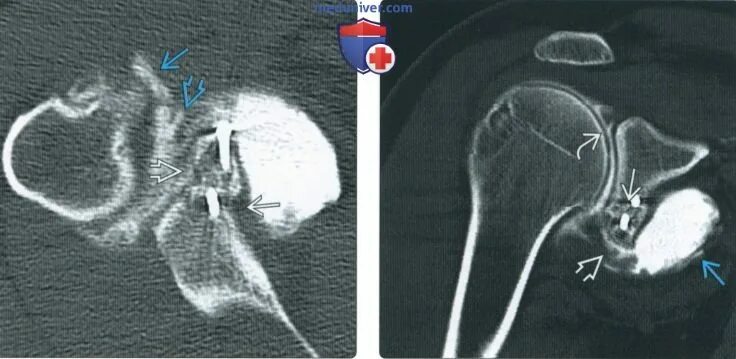

Нестабильность плечевого сустава мкб